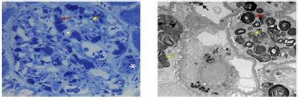

Um paciente de 32 anos de idade foi diagnosticado,

recentemente, com hipertensão de diagnóstico (PA =

160 mmHg x 90 mmHg) e hematúria microscópica repetida e

confirmada. Exames complementares revelaram creatinina

sérica = 1,0 mg/dL e proteinúria na urina de 24 horas =

650 mg. Ele foi submetido a biópsia renal, segundo a figura

apresentada, que confirmou o diagnóstico de nefropatia por

IgA com pontuação MEST-C M1, E1, S1, T1, С.